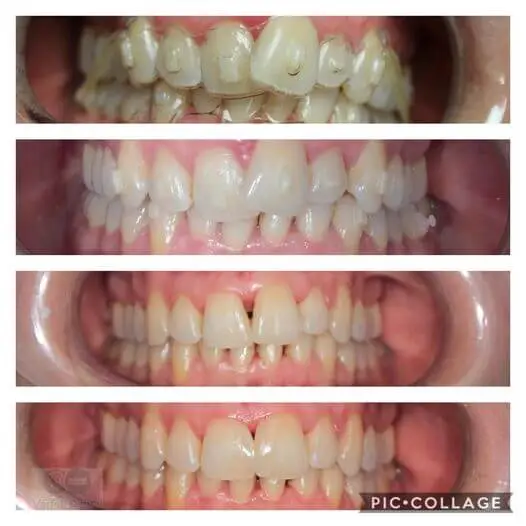

Szájrehabilitáció

Teljes szájrehabilitáció, melynek során megszüntettük az alábbi problémákat: rágózónák hiánya mindkét oldalt, emiatt elkopott fogazat, valamint réses, kicsi fogak.

Kezelés másfél évet ölelt fel. Igazi csapatmunka volt: dr kolarovszki béla 2-2 implantátumot ültetett be az alsó állcsontba. Ezt követte a tervezés, majd a fogak preparálása, ideiglenes pótlás, amjd végleges pótlás. A végén pedig 2 db tabletop betét.

A munka során digitális technikát alkalmaztunk( csonkok szkennelése), labor is digiálisan dolgozott és emelte meg a harapást.

Szerencsére meg tudtuk úgy oldani hogy voltak fogak (összesen 6) amit nem is kellett lecsiszolni, megmaradhattak eredeti formájukban.